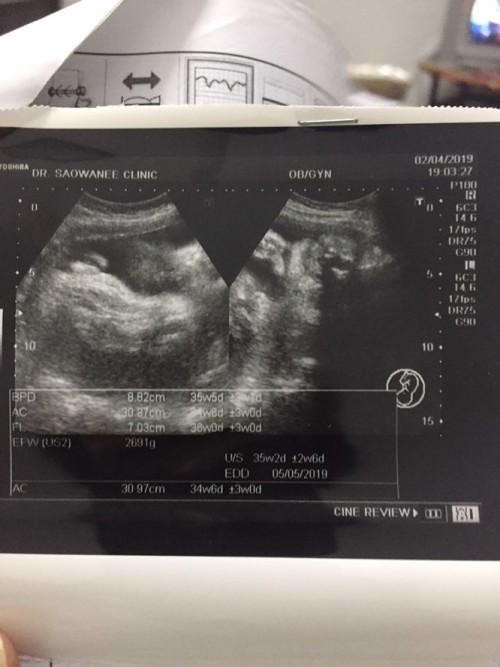

ใบซาวด์

ขอดูใบซาวด์แม่เพศ ชาย หญิง หน่อยค่ะ